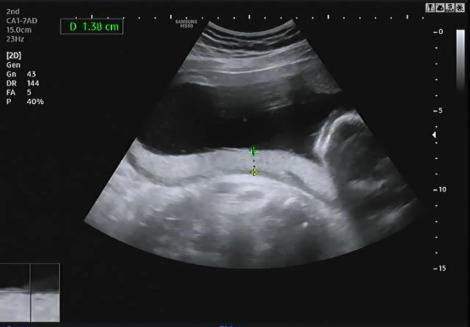

침대에 누워 복부초음파를 보는데 먼저 자궁경부 길이 등을 확인하고 양수량이 적당히 있는지 확인을 했다. 다행히 나는 자궁경부 길이가 4.22cm고 양수량도 적당히 있어서 조산위험이 없다고 했다. 자궁경부 길이가 짧을수록 조산위험이 크기 때문에 절대 안정이 필요하다.